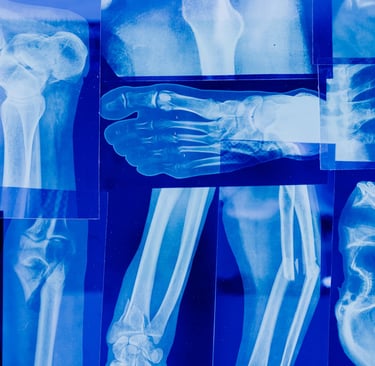

Durante la menopausia, la disminución de estrógenos acelera la pérdida de masa ósea, aumentando el riesgo de osteoporosis y fracturas. La alimentación juega un papel crucial en esta etapa, no solo para frenar esa pérdida, sino también para mantener huesos fuertes y funcionales a largo plazo.

Disminuye el riesgo de fracturas.